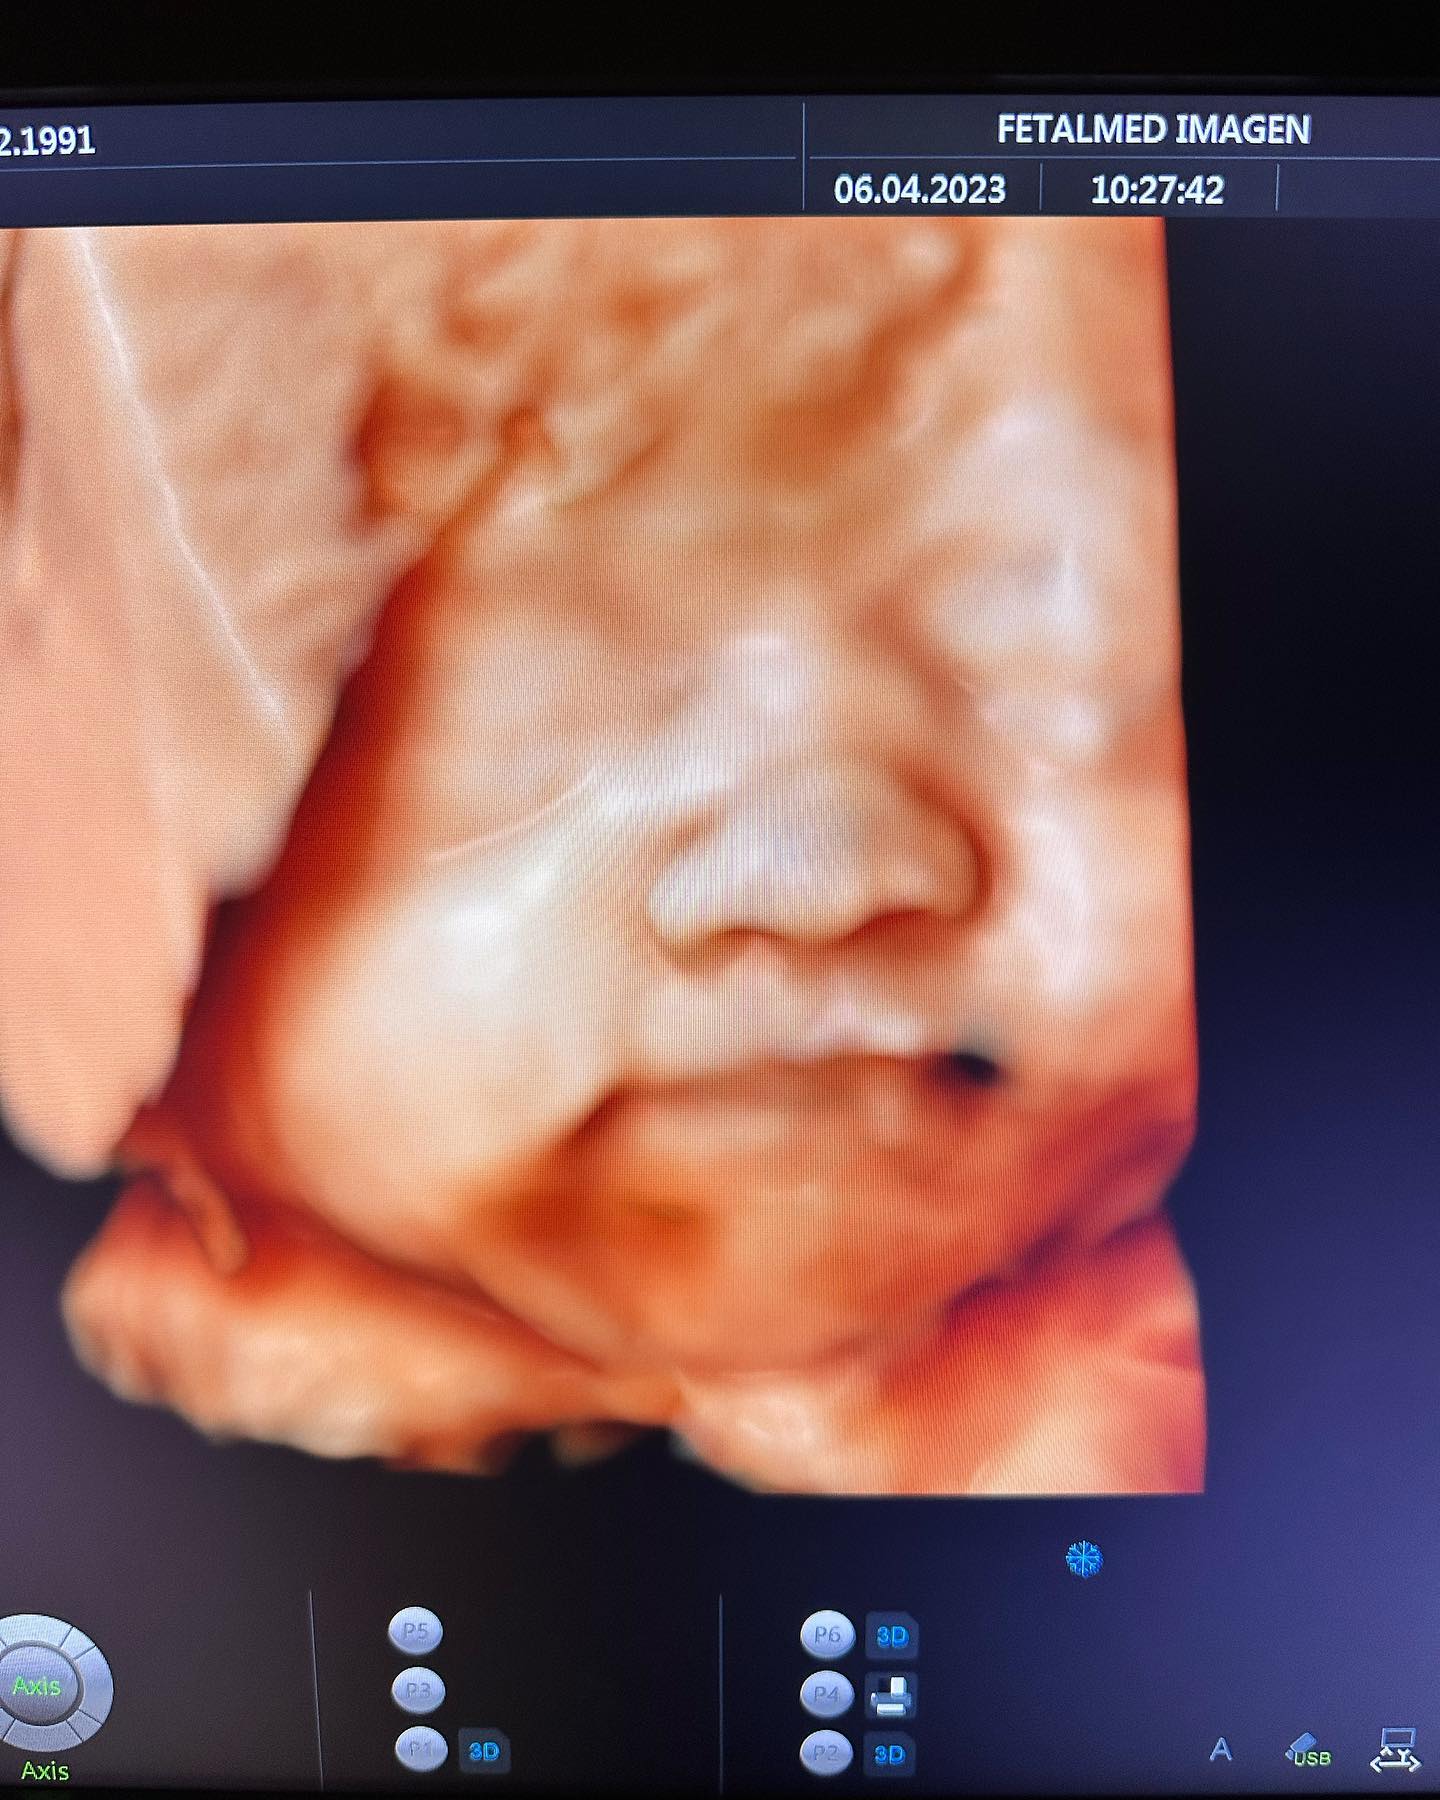

Es por lo mismo que recientemente la ex gimnasta encantó a sus seguidores luego de compartir unas fotitos en la que luce su guatita de 7 meses y medio, además de la última ecografía, en la que se puede ver en alta definición el rostro de su retoña.

«Semana 30 🤰🏻 cada vez la ANTO crece más mide 39 cm y pesa 1 kilo y medio. Pueden deslizar para el lado derecho y ver las fotos de ayer en su ecografía», comenzó escribiendo Vale Roth para acompañar los registros en su cuenta de Instagram.